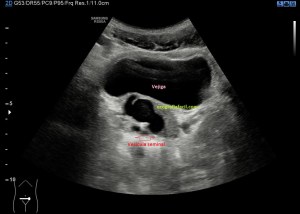

En esta imagen 3 ves un corte axial, o eje corto, del compartimento 1, donde no se objetiva correctamente el tabique separador de los tendones en la zona patológica, donde ves el retináculo engrosado, con líquido en la vaina, compara con la apariencia normal contralateral y almacena en tu memoria…